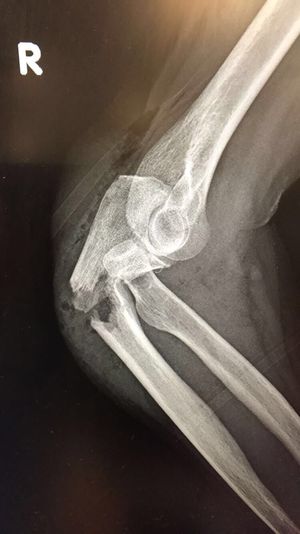

Fracture

89 year old woman sustained a fall

Orthopedic

Arm Surgery